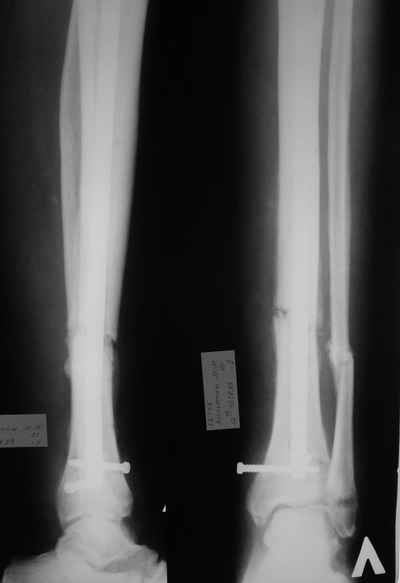

Открытый перелом- пхо+стержневой аппарат-штифтование. Через 4 месяца отек, температура 39….

Удален штифт-резекция+билокальный остеосинтез. Выращивание дистракционного регенерата

Повторное штифтование с рассверливанием. Оставлен дистально «легкий» аппарат для создания компрессии сближенных опилов на 4 недели.